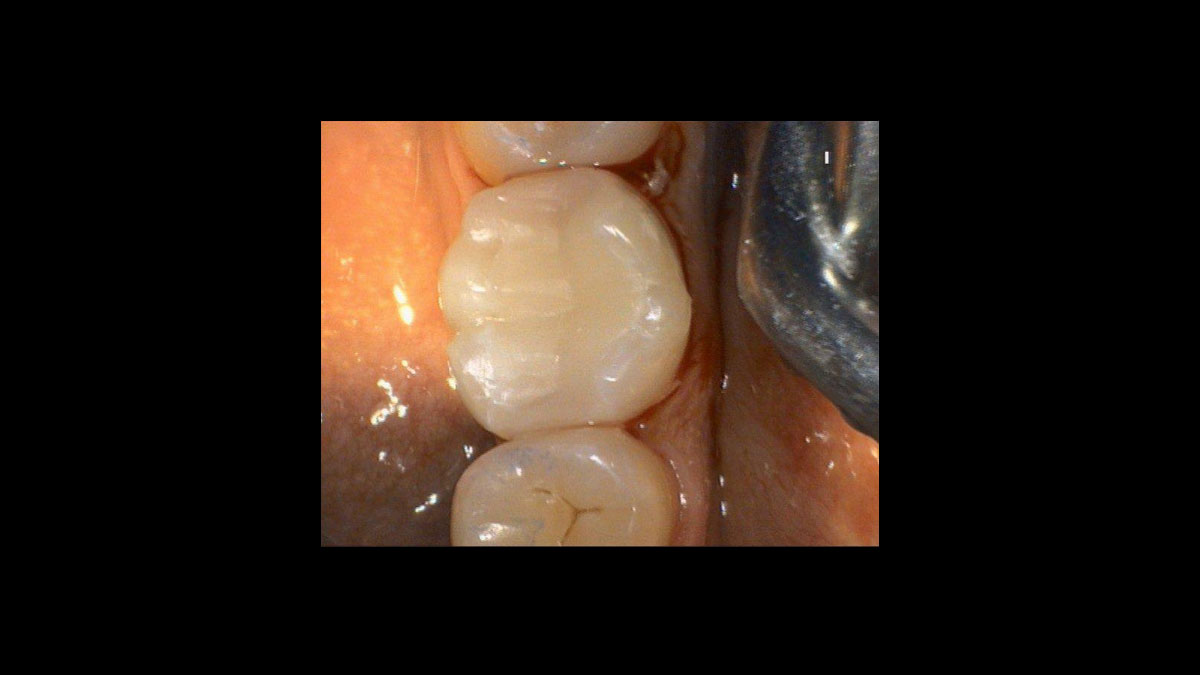

Cirugía

Las siguientes aplicaciones se presentan en los videos y las imágenes:

• Cirugía